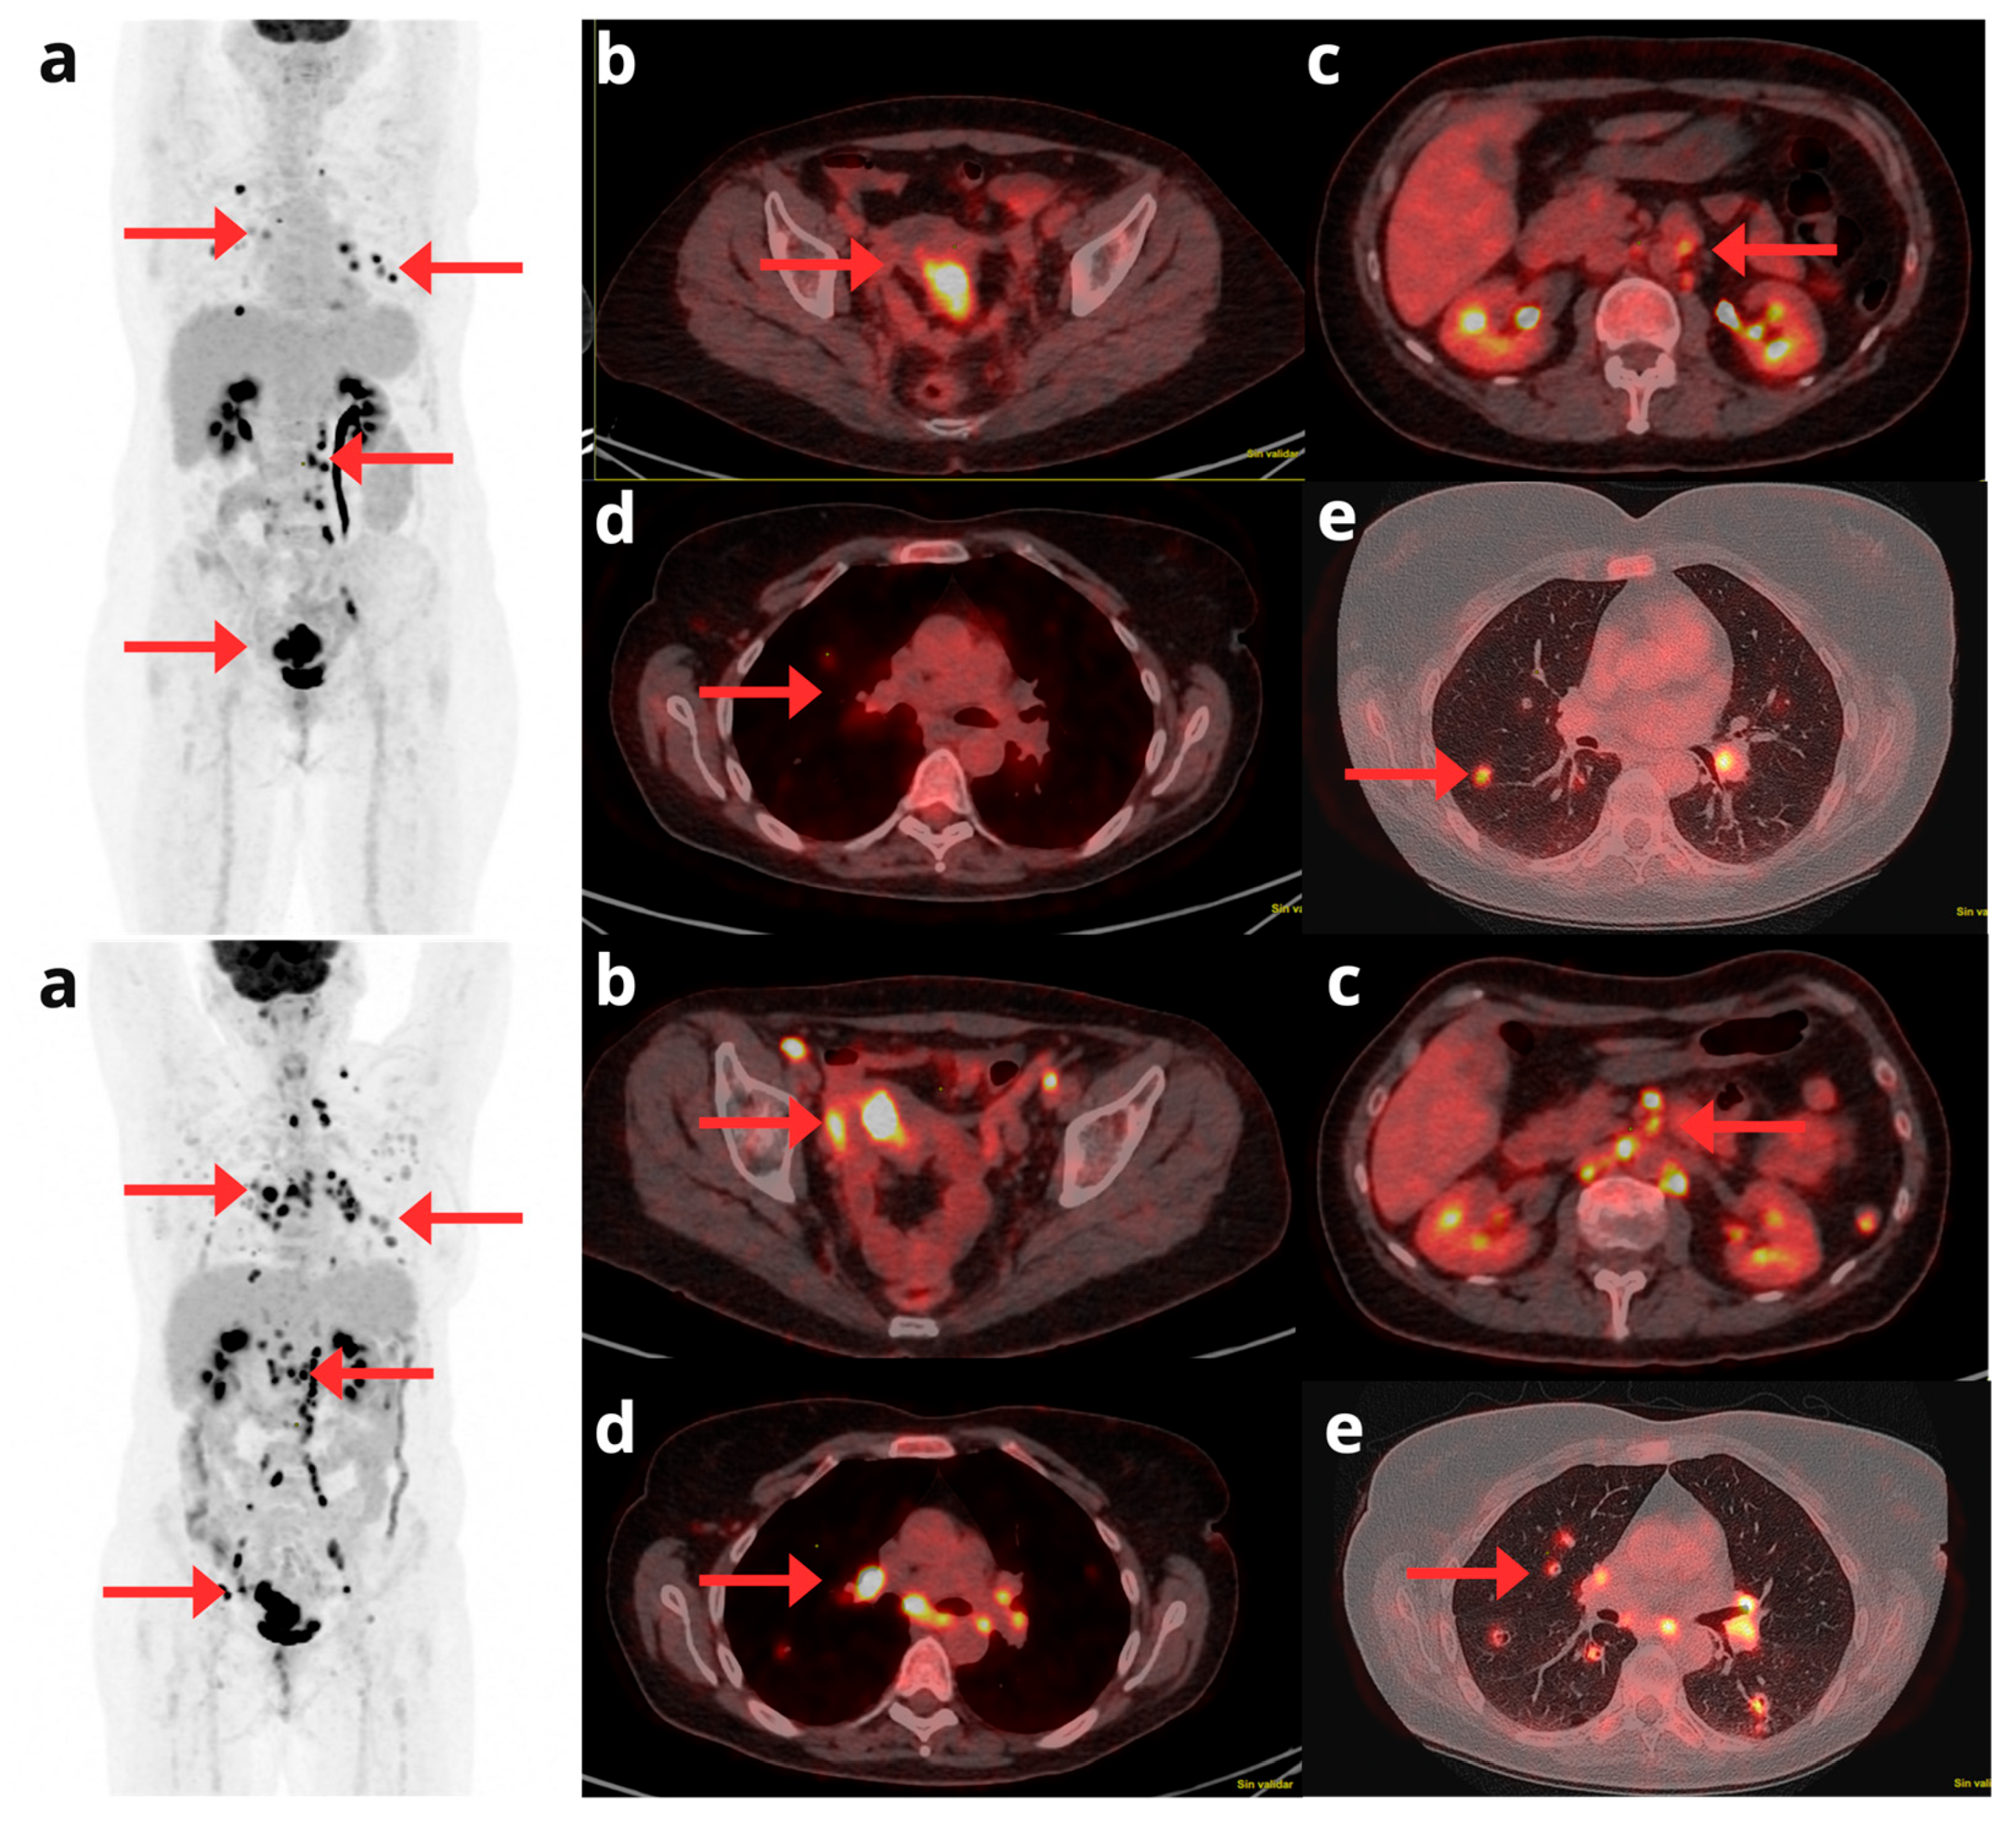

- Kurra, V.; Krajewski, K.M.; Jagannathan, J.; Giardino, A.; Berlin, S.; Ramaiya, N. Typical and Atypical Metastatic Sites of Recurrent Endometrial Carcinoma. Cancer Imaging 2013, 13, 113–122. [CrossRef]

- Kadkhodayan, S.; Shahriari, S.; Treglia, G.; Yousefi, Z.; Sadeghi, R. Accuracy of 18-F-FDG PET Imaging in the Follow up of Endometrial Cancer Patients: Systematic Review and Meta-Analysis of the Literature. Gynecol. Oncol. 2013, 128, 397–404. [CrossRef]

- Kirchner, J.; Sawicki, L.M.; Suntharalingam, S.; Grueneisen, J.; Ruhlmann, V.; Aktas, B.; Deuschl, C.; Herrmann, K.; Antoch, G.; Forsting, M.; et al. Whole-Body Staging of Female Patients with Recurrent Pelvic Malignancies: Ultra-Fast 18F-FDG PET/MRI Compared to 18F-FDG PET/CT and CT. PLoS One 2017, 12, e0172553. [CrossRef]

- Zheng, M.; Xie, D.; Pan, C.; Xu, Y.; Yu, W. Diagnostic Value of 18F-FDG PET/MRI in Recurrent Pelvis Malignancies of Female Patients: A Systematic Review and Meta-Analysis. Nucl Med Commun 2018, 39, 479–485. [CrossRef]

- Queiroz, M.A.; Kubik-Huch, R.A.; Hauser, N.; Freiwald-Chilla, B.; von Schulthess, G.; Froehlich, J.M.; Veit-Haibach, P. PET/MRI and PET/CT in Advanced Gynaecological Tumours: Initial Experience and Comparison. Eur Radiol 2015, 25, 2222–2230. [CrossRef]

- Sawicki, L.M.; Kirchner, J.; Grueneisen, J.; Ruhlmann, V.; Aktas, B.; Schaarschmidt, B.M.; Forsting, M.; Herrmann, K.; Antoch, G.; Umutlu, L. Comparison of 18F–FDG PET/MRI and MRI Alone for Whole-Body Staging and Potential Impact on Therapeutic Management of Women with Suspected Recurrent Pelvic Cancer: A Follow-up Study. Eur J Nucl Med Mol Imaging 2018, 45, 622–629. [CrossRef]

- Lin, G.; Lai, C.-H.; Yen, T.-C. Emerging Molecular Imaging Techniques in Gynecologic Oncology. PET Clinics 2018, 13, 289–299. [CrossRef]